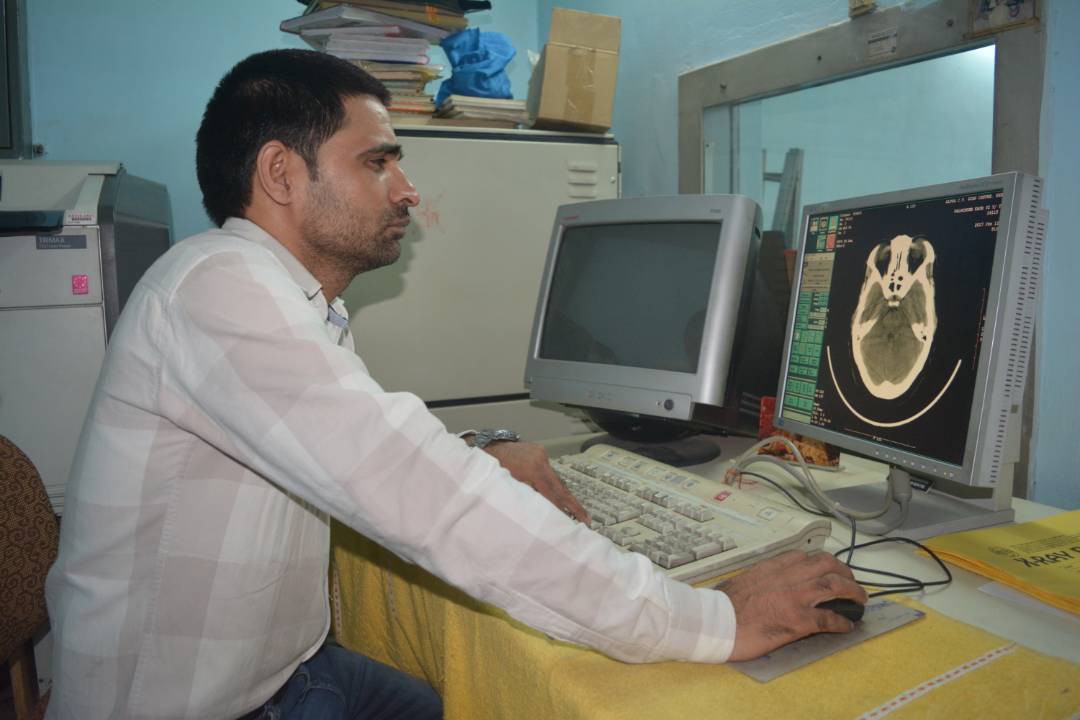

C.T. SCAN

Multislice CT Scan machine of Wipro GE brightspeed